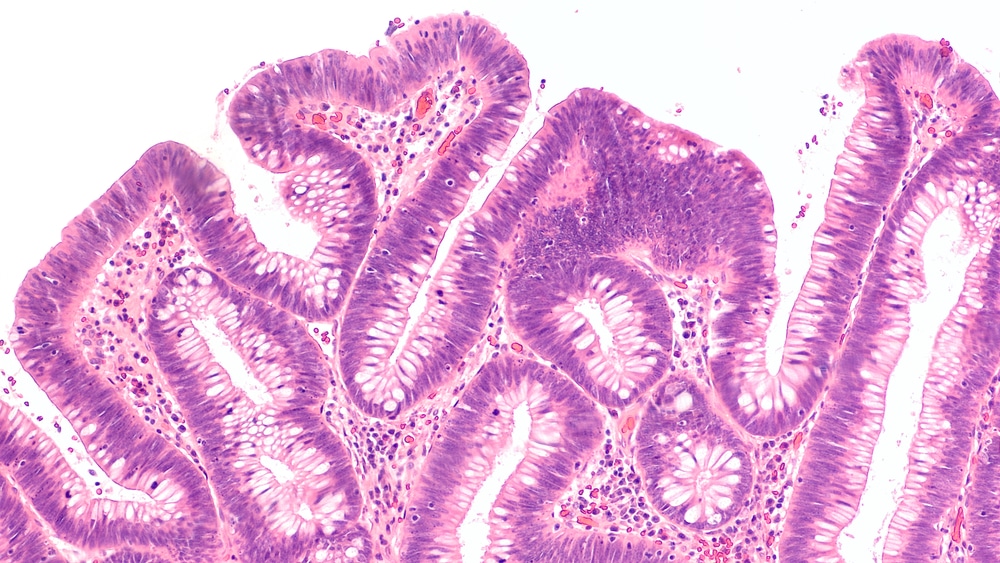

Les cellules du cancer colorectal

Cancer colorectal : l’importance du dépistage en chiffres

À la Clinique 1037, ça fait partie de notre mission de sensibiliser la population au sujet du dépistage...